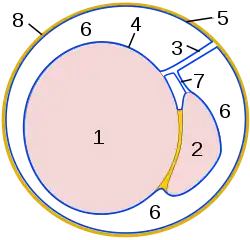

Diagram of a cross-section of a testicle. 1. Cavity of tunica vaginalis, 2. Visceral lamina, 3. Parietal lamina. | |

The tunica vaginalis is a pouch of[2] serous membrane[3] within the scrotum that lines the testis and epididymis (visceral layer of tunica vaginalis), and the inner surface of the scrotum (parietal layer of tunica vaginalis). It is the outermost of the three layers that constitute the capsule of the testis, with the tunica albuginea of penis situated beneath it.

Visceral layer

The visceral layer of tunica vaginalis of testis (lamina visceralis tunicae vaginalis testis)[4] is the portion of the tunica vaginalis that covers the testis and epididymis. It is the superficial-most of the three layers that constitute the capsule of the testis, with the tunica albuginea of testis situated deep to it. Posteriorly, the visceral layer does not line the surface of the testis - instead, it passes onto the epididymis where the latter attaches to the testis before continuing onto the inner surface of the scrotum as the parietal layer.[5]

Parietal layer

The parietal layer of tunica vaginalis of testis (lamina parietalis tunicae vaginalis testis)[6] is the portion of the tunica vaginalis that lines the inner surface of the scrotum.[5] It is supported by the internal spermatic fascia.[6]

Cavity of the tunica vaginalis

The cavity of the tunica vaginalis[5] (also: cavum of the tunica vaginalis,[5] or cavum vaginale) is the cavity between the visceral layer and the parietal layer of tunica vaginalis. It is normally occupied by a small amount of clear, lightly coloured fluid.[5]